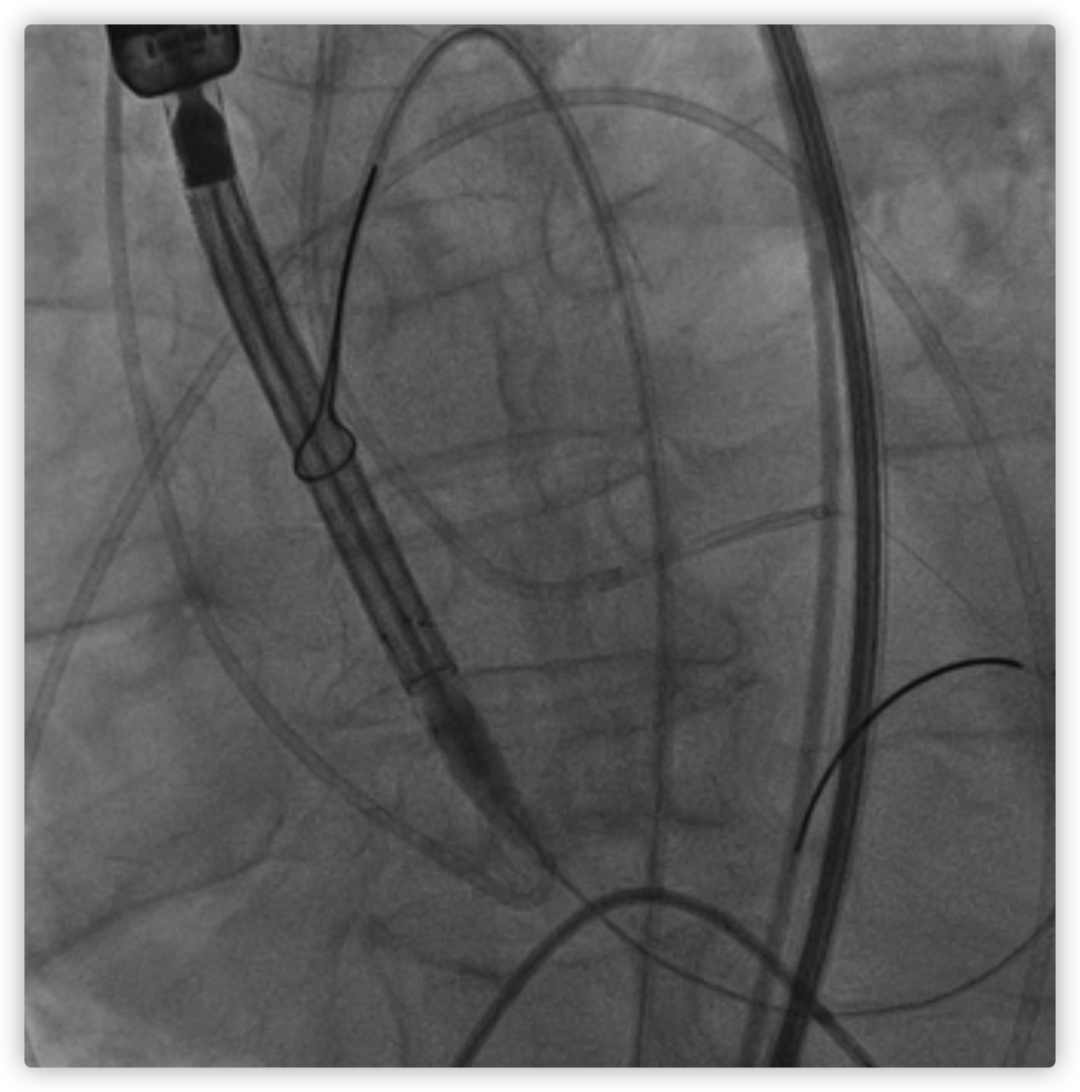

26VenusAplus+snare

瓣膜内22mm球囊后扩张,左冠无显影

LM烟囱支架植入4.0*30mm